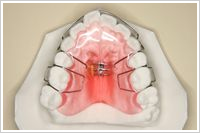

床矯正治療

床矯正治療では、基本的には永久歯は抜かずに、顎を少し拡げて歯をきれいに並べます。治療には、下の写真のような入れ歯にネジのついた装置を使います。取り外し式なので日常生活は今までとあまり変わりません。痛みはほとんどありません。基本的には学校には装置をつけていかないので、街中でこの床矯正装置を見ることはほとんどないのです。

▼床矯正装置

床矯正治療に用いられる装置は、入れ歯と構造がよく似ていて、自由に取り外しができます。赤い部分はプラスチックでできていて床(しょう)と呼ばれます。弱い力の作用で歯を動かしたり、顎を拡げたりするので、痛みはほとんどありません。顎を拡げるといっても顔が大きくなるわけではありません。1日に12時間以上装着(中学生以上の場合は、20時間以上)していれば大丈夫です。 頬づえや猫背、開口などの悪い癖は治しておきましょう。